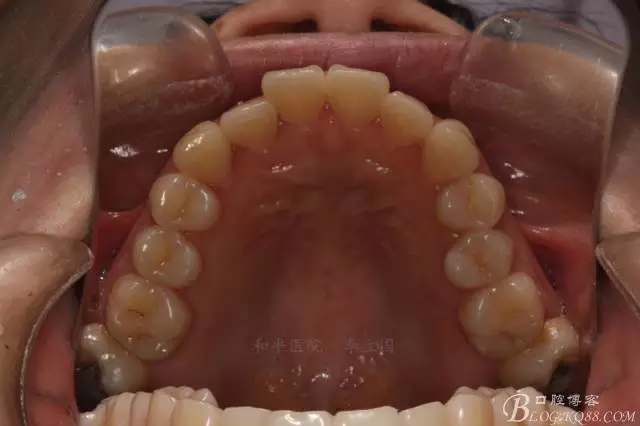

如圖,該病例為簡單排齊病例,但77鎖合是矯治中的關鍵所在,你會怎么處理?

該病例主要為17、27頰側(cè)位同時伴有伸長,當然種植支抗可以解決,但還有簡單實用的辦法嗎?如圖,在橫腭桿遠中延伸出牽引鉤,位置盡量遠離合平面,7粘舌側(cè)扣,牽引力的方向為壓低及舌向,下圖為兩個月的效果,17已到位,27還未到位。